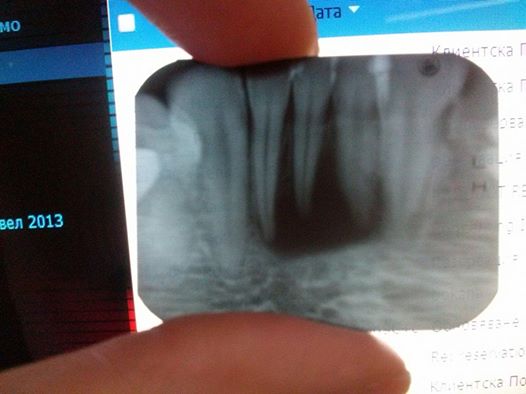

Здравейте Д-р Косев, Прикачила съм снимка на предните си три долни зъби. Има образование което не могат в моя град да преценят какво е точно. Всеки зъболекър ми казва различно и ми предлага различни решения. Попринцип тези зъби не ме болят, но ми излиза гнойна торба на венеца, пия антибиотик и минава, но след три четири седмици се появява отново и става по-зле и по-зле. Много ще Ви благодарна ако ми отделите 5 минути и кажете и своето мнение. Поздрави!

- 10262242_10201924265128008_1769237211353980783_n.jpg (25.05 KiB) Прегледано 527 пъти

Скъпа приятелко, тава е или кистозно или грануломатозно образование което обхваща трите фронтални резеца. Това възпаление е започнало най-вероятно от централният резец, поне така си мисля от снимката. Причината е доста стара травма или пародонтит. Ако аз трабва да решавам този проблем сигурно ще пристъпя към много добро ендодонско/терапевтично/ лечение на трите зъба. Обикновенно прогнозата е добра , но пак с уговорката за екзактно лечение. След това се преценява ако има подвижност за временно или постоянно шиниране на фронталните зъби. Хубаво е да се проследяват във времето с рентгенографии. Потърси добър ендодонтист! Късмет.